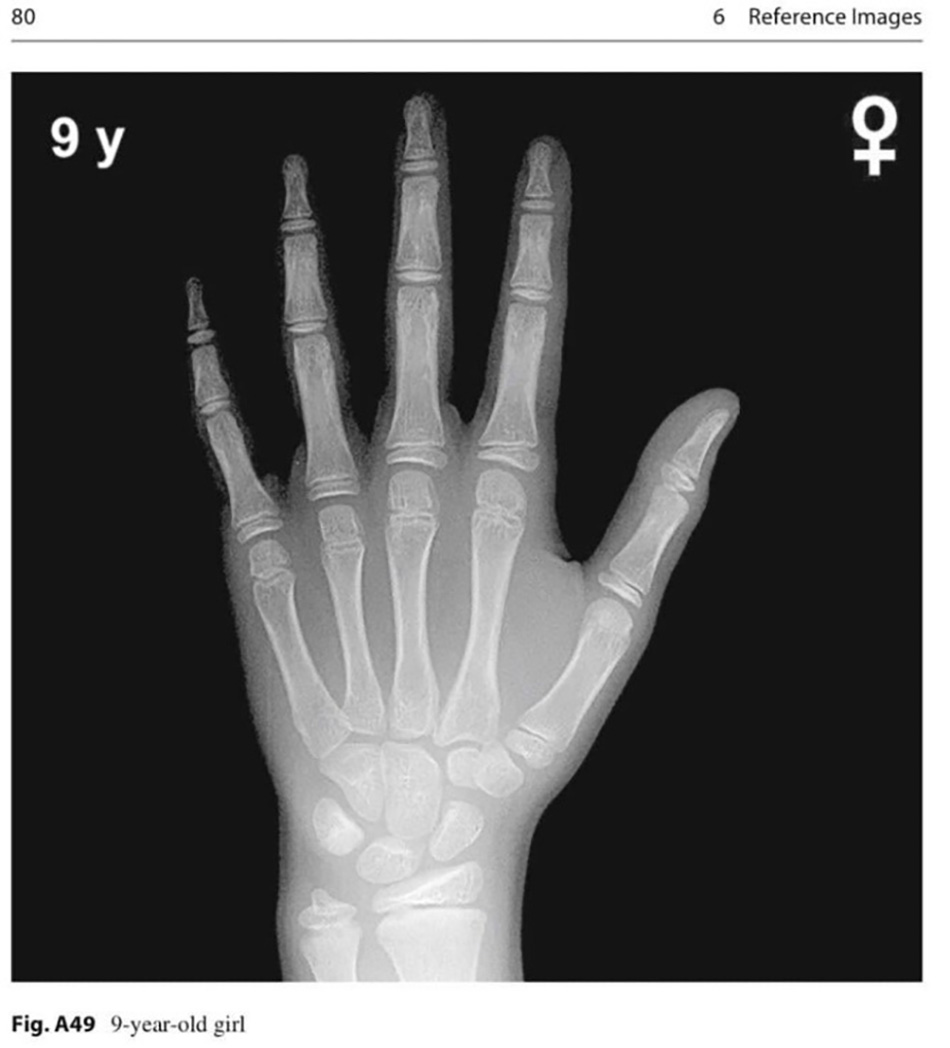

With over 15 years of experience in diagnosing and treating early puberty, the Internal Medicine Department at FV Hospital provides a comprehensive approach. Children are first examined by endocrinology specialists, who conduct essential evaluations to determine a diagnosis. These include breast and abdominal ultrasounds to assess the uterus and ovaries in girls, testicular ultrasound in boys, and a hand X-ray to determine bone age.

Example of a hand X-ray used to assess bone age in children